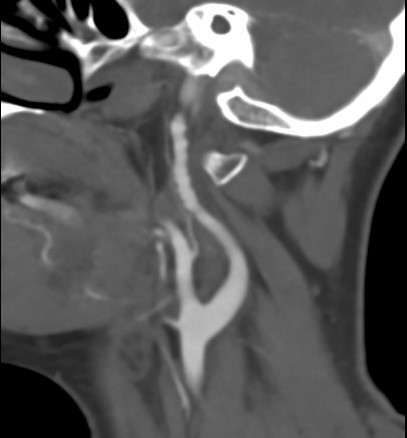

- CT angiography – Computerized tomography angiography (i.e. CTA) is increasingly being used to scan for fibromuscular dysplasia. Surprisingly, this technique is still not well validated, although better imaging techniques and reconstruction programs offer very good views of the renal arteries:

-

Imaging of cerebral FMD can be done with duplex ultrasonography (that has a low sensitivity / specificity in this site), CT angiography or MR angiography. Notably, FMD patients should undergo at least one brain imaging. A 2017 analysis of the FMD registry has shown that 12.9% of women with fibromuscular dysplasia have brain aneurysms. Of these over 40% are larger than 5mm. Thus, identifying these aneurysms matters.